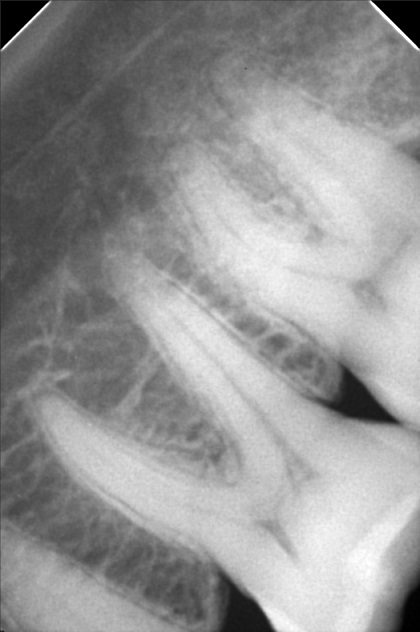

Edit Record Check our patient data records. Add patient information Patient Info Profile picture Last Name First Name Middle Name Birthdate Age Street Barangay City Country Zip Code Contact number Email Procedure 4/8/22- check up ***pano/ ceph ***#46 exo presence of lip tie 04/02/22 odontectomy 48/38- class 3/ mesioverted exo 46/ tongue tie/ ankyglossia frenectomy (laser) pt under IV CS Ozone therapy ****ff up after 2 weeks/ ***for orthodontic treatment 06/16/22 LC 24 OD/ CAOH LC 47 M op/ OZONE 1/11/23- Adj , 16niti Upper, Rotational Wedge # 42D , reattached #35 11/04/22-OP/LC 15,36,26,/mta/XRAY 11/16/22-InsOfBraces/Niti 14/14(MBT0.22) 12/07/22-adj 01/11/23- adj 04/12/23- same wire U/ Lower NiTi 16/ reattached #34,15/IPR between #32-33 05/05/23- U same wire; L SS-16; Resto #14DO, #15MOD, #16D 06/07/23- Informed Consent Resto #14DO (redo) Ortho UL same wire Remove RW #33 Monkey elastics #13-#23-#33-#43 07/19/23- Lc 36 occusal, lingual 18 ss U 18ss l rw 33 distal 08/18/23- 09/15/23- same wire #22 extrude 10/13/23 - adjustment, same wire - RW on #12 mesial 12/13/23-16X16 L -Penguin Cross Elastic -Upper to Right -Lower to left 01/12/24- adjustment same wires X-elastics on posterior Pms FOR removal on APRIL 02/21/24 same wire chain upper and lower rabbit to 3's to 4's 03/22/24 same wire rabbit 43 to 25 chipmunk 13 to 45 RW #45 distal 04/19/24 Removal of braces for retainers( vacuumed retainers) OP w/ flouride impression U/L 07/19/25 op with air polisher 03/18/26 Summer smile promo LC #14 - M,O, D + caoH + GI #15 - M,O,D + desen #16- M, O, Li + caoH + GI 03/26/26 Redo 04/08/26 check up 05/14/26 LC #16- fiber + mta File dana46.jpg File 2 file_0001_1_2.jpg File 3 file_0001_3.jpg File 4 dana_aguto.jpg File 5 dana_aguto_02.jpg File 6 dana_aguto_03.jpg File 7 dana_guto_04.jpg File 8 img_20240406_103512.jpg File 9 File 10 File 11 File 12 File 13 File 14 File 15 File 16 File 17 File 18 File 19 File 20 Retain Record Retain Record Yes No Save Your Changes